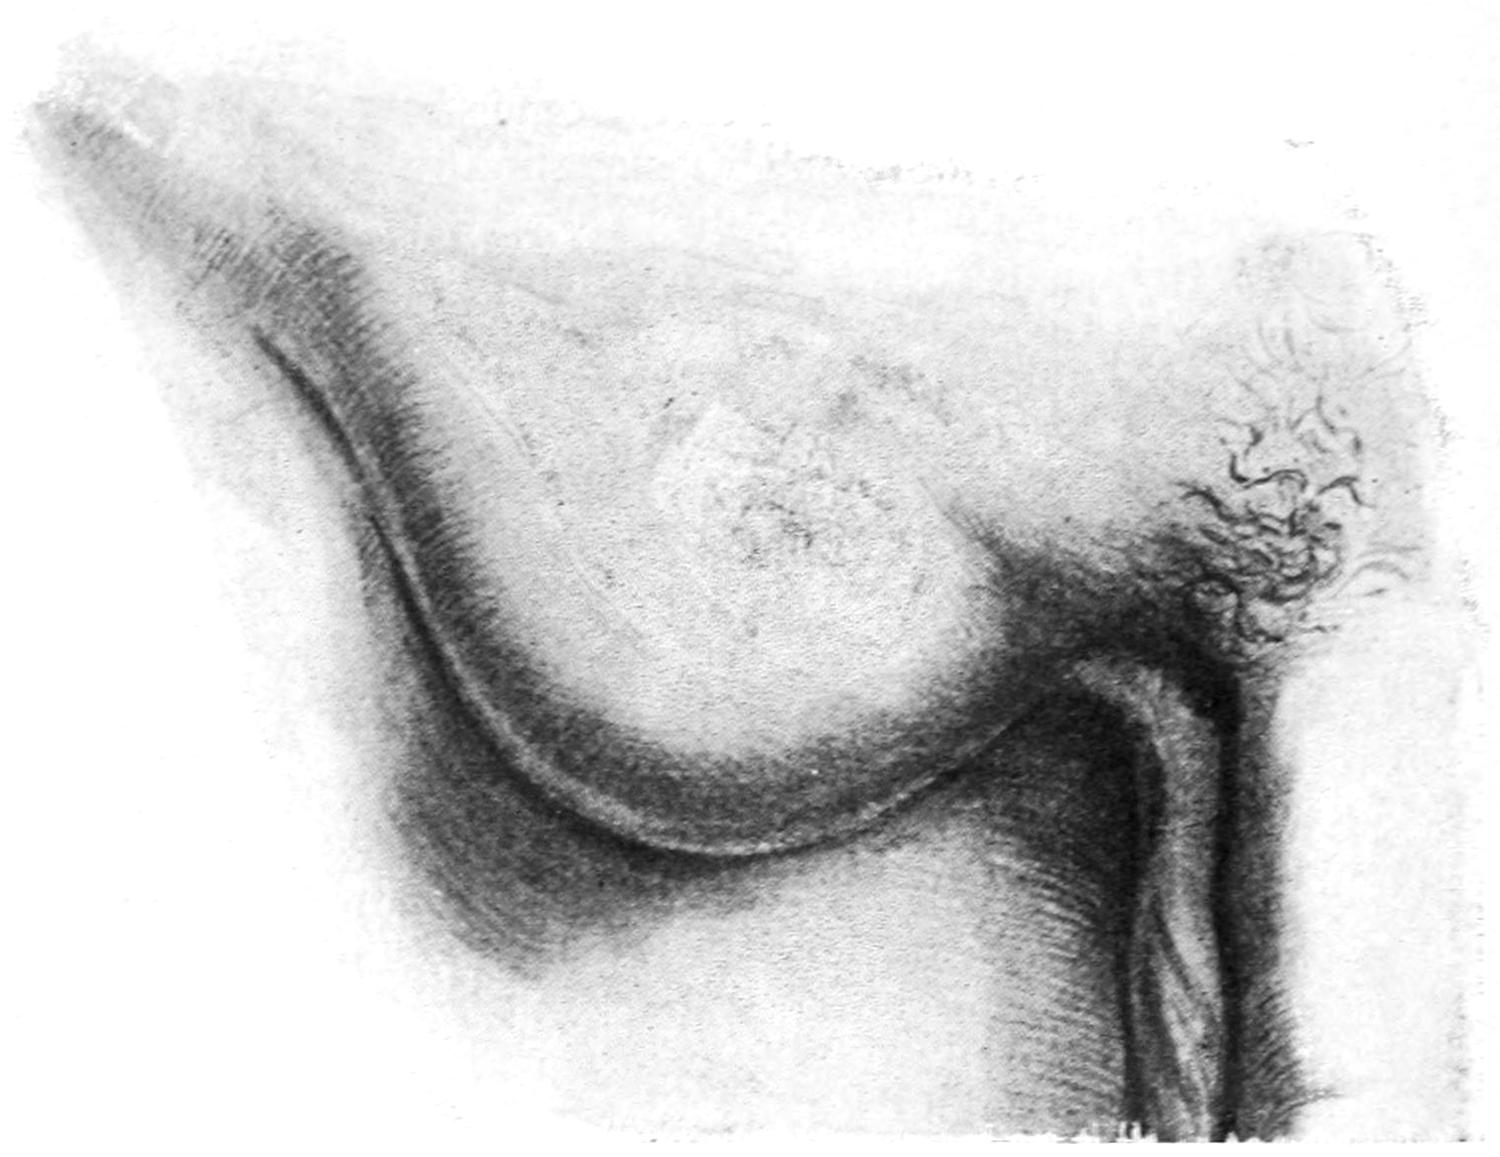

THE BREAST 755